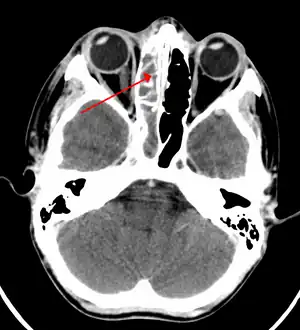

| A CT scan showing sinusitis of the ethmoid sinus | |